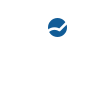

슬개골 탈구 내측 4기, 십자인대 질환

- Case: DFO + TPLO + TTT 수술

- 9살 9.5kg 시바이누

현증인 십자인대 질환에만 집중할 경우 십자인대 질환에 대한 교정 수술인 TPLO만 진행할 수 있습니다.

현재, 슬개골탈구 교정이 같이 필요한 환자의 경우 DFO 수술을 같이 하고 있습니다.

이럴 경우 환자의 보행이 현저하게 개선이 되고 다시 마음껏 뛰어다닐 수 있습니다.

DFO: Distal Femoral Osteotomy, 대퇴골 골기형을 교정하는 수술